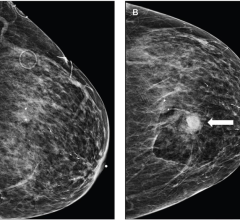

Despite decades of progress in breast imaging, one challenge continues to test even the most skilled radiologists ...